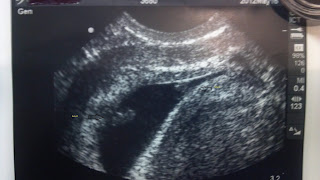

This is our Baby A

We had a great ultrasound yesterday morning! It was completely worth getting up at 5am and fighting the rain of Tropical Storm Debby to get to the Naval Hospital. The tropical storm is doing a fantastic job of flooding out our area! The base was almost under water! But we saw on our ultrasound that our babies sure are active! We even witnessed one of the babies (Baby B) kicking the other baby (Baby A). I couldn't believe they were fighting already!! I also found out that when my bladder is full - it's pressing on Baby A and he/she doesn't like that very much. Baby A is my lower baby, closer to my cervix and Baby B is my high riding baby.

And this is our Baby B

It's so amazing how fast they grow! At my ultrasound on June 8th they were barely 3 cm long, and they have doubled in size to a little over 6 cms long now!! Insane!! But we got to see our beautiful babies and their healthy heartbeats. The technician was able to get all the information she needed for the doctor to determine if they share a Placenta or not, which will determine if we are able to deliever at the Naval Hospital. If they share a Placenta we are considered Higher Risk and will be referred to a High Risk OB. But right now - they are perfectly healthy! We have a genetic screening ultrasound on Friday and I can't wait to see them again. I love seeing them! We also have an appointment with a Dr on the 2nd - just the normal 4 week follow up care.